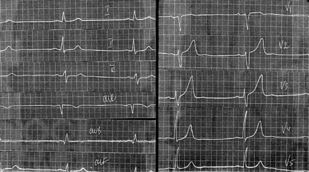

Инфарктоподобные изменения электрокардиограммы при различных заболеваниях

В пособии проанализированы электрокардиограммы больных с заболеваниями, симулирующими инфаркт миокарда, такими как гипертрофическая кардиомиопатия, тромбоэмболия легочной артерии, синдром WPW, склеродермия, феохромоцитома и др. Пособие является опытом обобщения авторами проблем трактовки электрокардиограмм с инфарктоподобными изменениями.